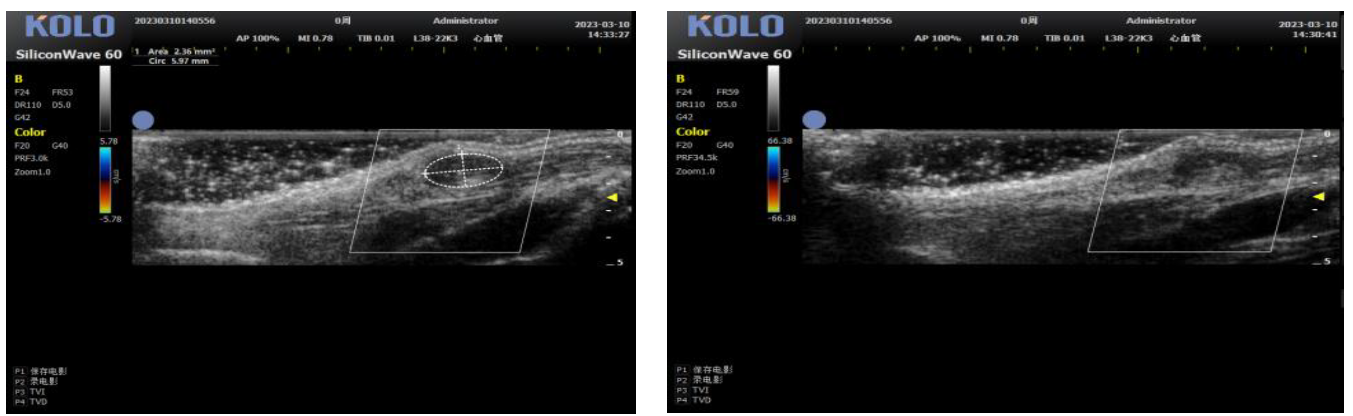

基于CMUT 半导体超声技术,集成多项发明专利,珂纳医疗精心研发出 SiliconWave 60 超高频小动物超声成像系统。该系统微米级的超高清分辨率,8-62 MHz 超宽频段和丰富灵敏的彩色多普勒功能为临床前科研用户观察小动物的心血管、腹部脏 器、浅表组织及胚胎等提供了清晰多彩的超声图像。系统的实时无创操作也为科研实验 的反复验证,长期动态观察等提供了极大的便利性。

二、研究案例

5肿瘤测量(肿瘤大小精确测量)